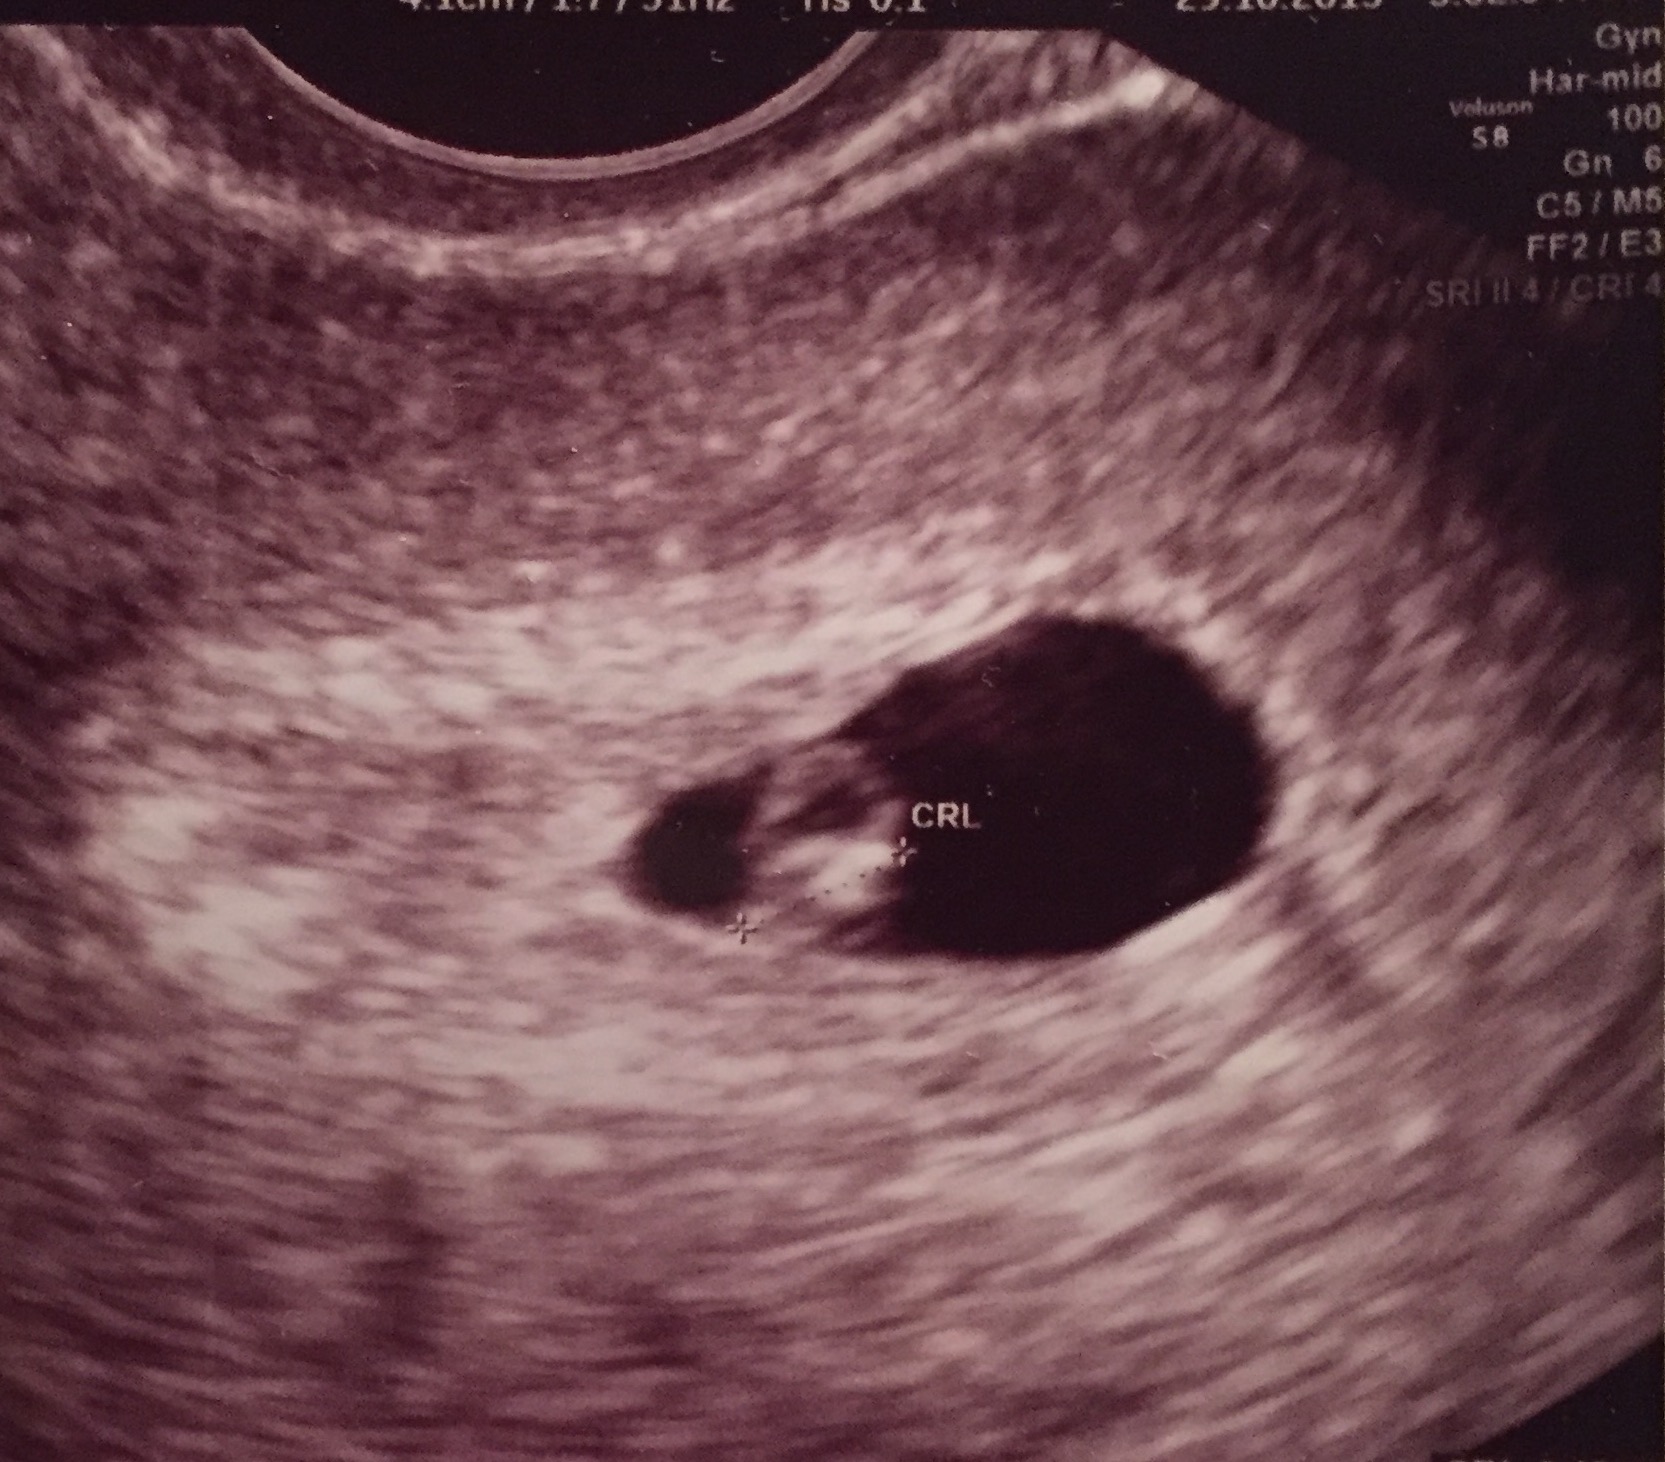

Alt supert med lille i magen. Såååå lykkelig<3 Ferdig på IVF-klinikken og på tide å bestille time hos fastlegen. Er ubrukelig på å tyde ul bilder. Men så tydelig et blinkende hjerte. <3

Det var "bare én" der nå, men det var heeelt greit, for den var så sterke og fine hjerteslag at vi begynte endelig å kjenne litt på en god magefølelse

124 nydelige slag i minuttet, 5 mm lang og allerede høyt elsket! Lille nurk på 6+2